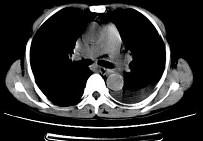

问题 女,55岁,胸痛伴咯血丝痰1周,胸部CT如图,最可能的诊断为 ( )

选项 A.转移性肺癌 B.左侧周围型肺癌并肺内转移 C.左侧中央型肺癌并肺内转移 D.多发性肺脓肿 E.结节病

答案 B